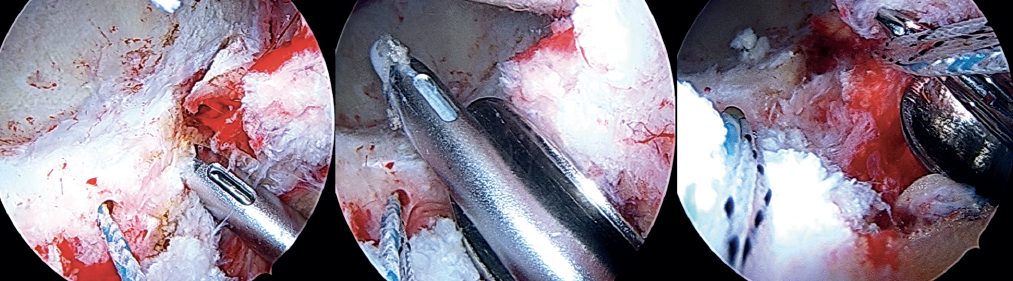

Insertion of the graft

Forceps are inserted from the posterior portal, taking care that they lie posterior to the last anchoring, and from the anterior modified portal we introduce the suture anchored to the anterior portion of the graft, likewise taking care that it lies anterior to the most anterior anchoring. Once within the joint, this suture is grasped with the forceps inserted from the posterior portal, and then traction is exerted posterior until it emerges from the posterolateral portal. Lastly, traction is continued to introduce the graft, making it emerge through the posterolateral portal. At this point, the anchoring preassembled in the graft is guided towards the pre-drilling made and is inserted, thereby fixing the most anterior portion of the graft in the case of using a knotless anchoring or extracting the suture and threading the tendon to then perform a knotted technique(Figure 12). After positioning and fixation of the most anterior portion of the graft, the filaments are passed around the graft in sequence, and are tightened little by little, maintaining traction from the posterolateral portal, and fixing and positioning the entire plasty from anterior to posterior (Figures 13 and 14). Once all these steps have been completed, the excess graft is radiofrequency amputated from the posterolateral portal. Lastly, the hip is evaluated dynamically in all the planes of motion, checking fixation, the position of the graft, and recreation of the sealing effect at the femoral head-neck junction with the acetabular labrum (Figure 15).

[[{"fid":"6608","view_mode":"default","fields":{"format":"default","alignment":""},"type":"media","field_deltas":{"8":{"format":"default","alignment":""}},"link_text":null,"attributes":{"class":"media-element file-default","data-delta":"8"}}]]

Finally, capsule closure is carried out using the routine technique. Table 1 describes the advantages and limitations of the procedure, and Table 2 indicates the key points to be taken into account.